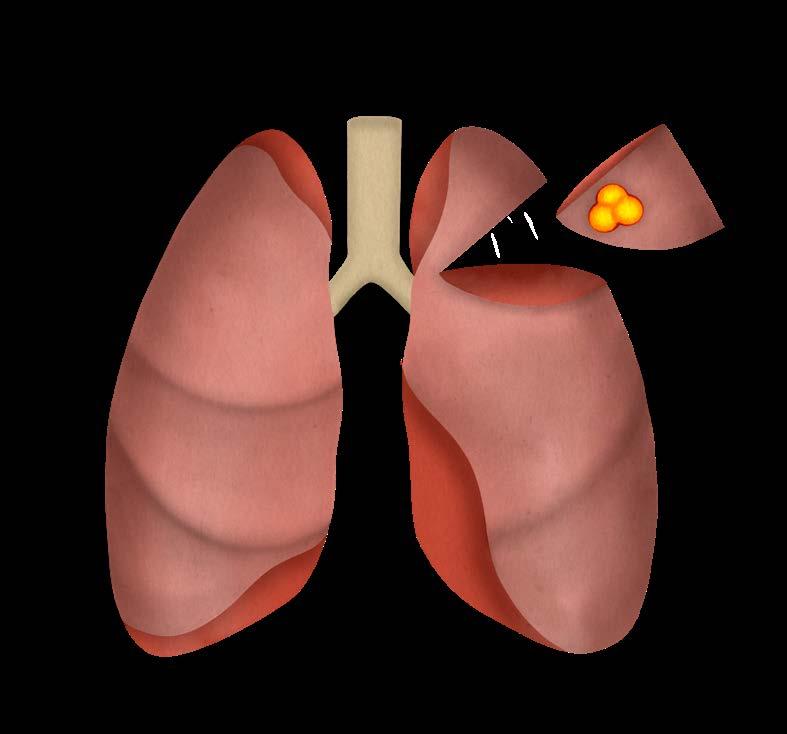

Mynd 6-1 Lítið lungnakrabbamein í hægra lunga (ör) sem fannst við skimun með tölvusneiðmyndum.

Með tilkomu tölvusneiðmyndatækni (TS) varð unnt að finna mun smærri hnúta í lungum en áður var mögulegt með hefðbundnum röntgenmyndum (mynd 6-1). Á síðustu áratugum hefur verið efnt til stórra framvirkra samstarfsverkefna, bæði í Bandaríkjunum og Evrópu. Fyrstu rannsóknir á skimun með TS voru gerðar í Japan og fyrsta alþjóðlega rannsóknin benti til þess að unnt væri að finna um